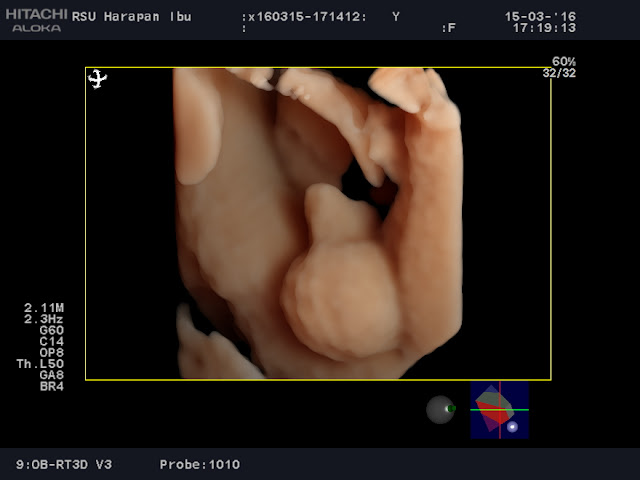

Berikut hasil pemeriksaan dengan menggunakan USG 4 Dimensi :